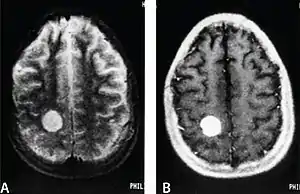

| MRI of a cardiac angiosarcoma that has metastasised to the brain. | |

Primary cardiac angiosarcoma

Primary cardiac angiosarcoma is an angiosarcoma that arises in the heart. Despite being very rare they are the most common malignant primary heart tumor with 10–25%[9][3] of cases being angiosarcomas. Symptoms may include shortness of breath, chest pain (46%[9]), hypotension and syncope. Superior vena cava syndrome is reportedly a complication of cardiac angiosarcoma.[7] Due to the non-specificity of symptoms and rarity of the disease it is often missed by doctors and initial diagnosis may be delayed. A 2012 study reported that 56% of patients presented with pericardial effusion with or without cardiac tamponade.[9] The most common finding on imaging is cardiomegaly. Prognosis is generally very poor with a mean survival rate of three months to four years following diagnosis.[7] Metastasis at time of diagnosis is common.[9]